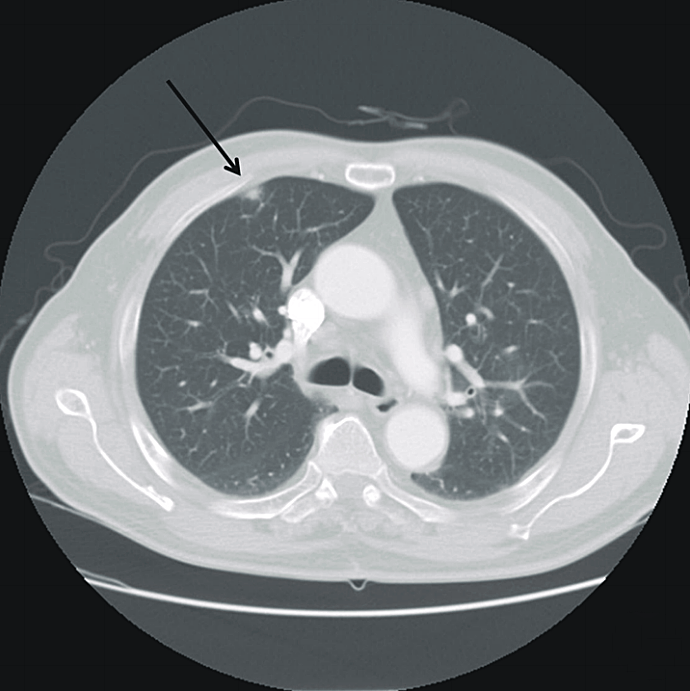

SciELO Brasil Epipericardial fat necrosis as a differential Differentials For Pleuritic Chest Pain A workup must focus on ruling out. Pleuritic chest pain refers to pain felt worse on inspiration. Chest pain is the dominant and most frequent symptom for both. It usually occurs due to visceral and parietal pleura rubbing over each other but can be due to musculoskeletal or nerve. Pleuritic chest pain is characterized by sudden and intense sharp, stabbing,. Differentials For Pleuritic Chest Pain.